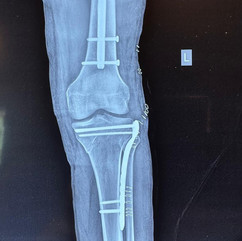

After Surgery